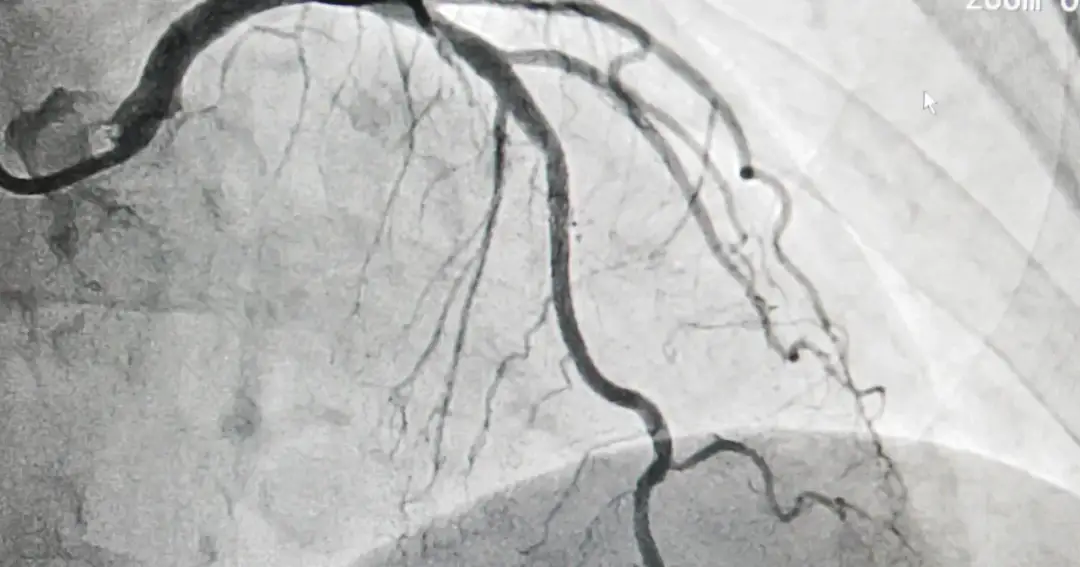

Koronografia - co to za badanie i jak może uratować Twoje serce

Poznaj, czym jest koronografia, co to za badanie i jak może pomóc w diagnozowaniu chorób serca, poprawiając Twoje zdrowie i jakość życia.